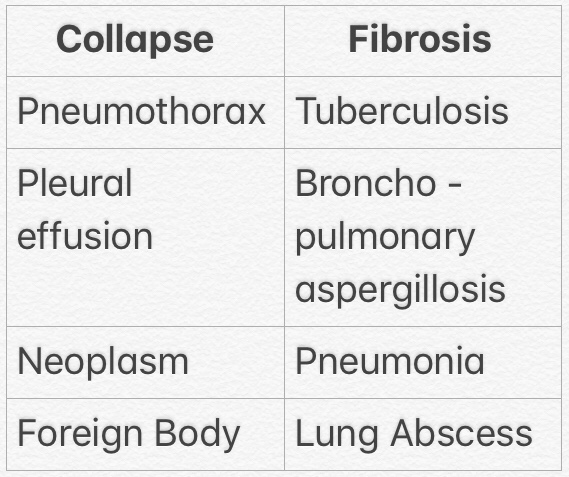

4) LUNG FIBROSIS & COLLAPSE

▪️Causes: